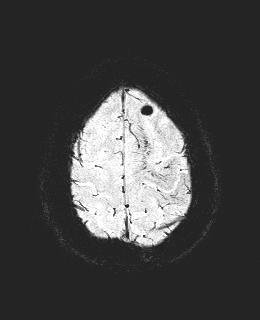

après l'IRM perso ils m'ont fait une artériographie pour affiner les résultats tellement c'est le bordel dans mon cerveau

cavernomes et malformation artério veineuse ... résultat rien à faire, je risque plus si on n'y touche je reste avec mes maux de têtes de la mort

ça fait 10 ans que j'ai pas revu le neurologue ça sert à rien ...

PS : j'ai retrouvé un cliché de mon cerveau

après l'IRM perso ils m'ont fait une artériographie pour affiner les résultats tellement c'est le bordel dans mon cerveau![]()

t'as un trou en haut, c'est ton cerveau qui joue de l'ocarina ?

un de mes cavernomes, si vous avez des tâches de naissances il y a de fortes chances que vous ayez ça aussi dans le cerveau